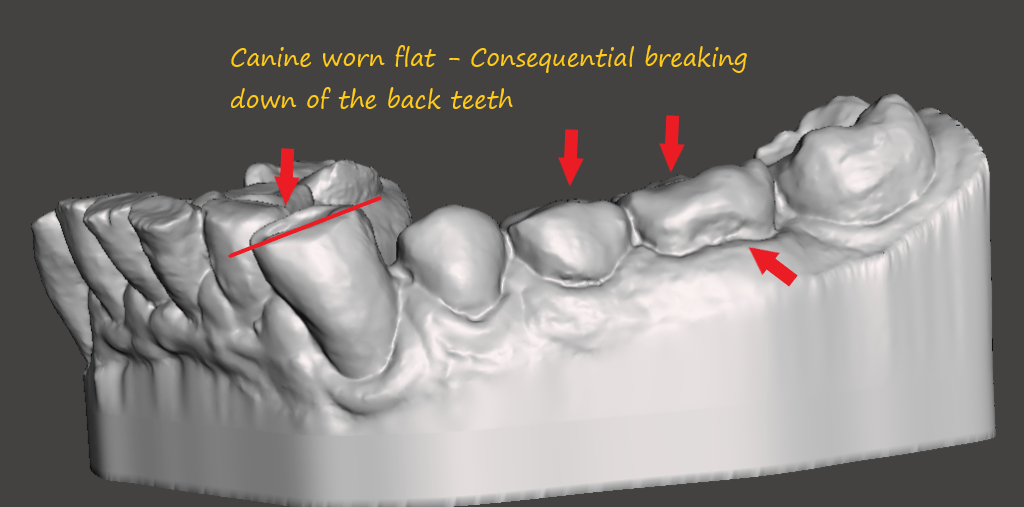

Back teeth are short with multiple roots, designed to crush hard things. The short, multiple roots serve to distribute the forces and you do not feel the tooth bending as much. Consequently molars can break each other in the opposing arch. This happens typically at night when you brux sideways.

Worn or mal (bad) occlusion

Centrals, laterals and canine all worn flat by bruxism. The anterior teeth are either flat and in more severe cases presents with a an inverted smile line

Without CANINE DISCLUSION back teeth will eventually get damaged when you grind your teeth sideways